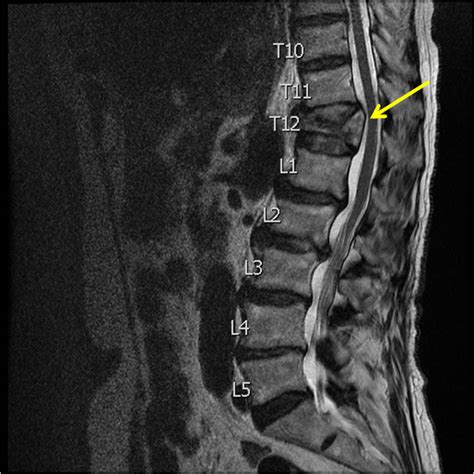

Imaging Tests

Imaging tests are crucial for confirming the diagnosis and determining the severity of the fracture.

• MRI Scans: MRIs are useful for evaluating soft tissues, such as ligaments and spinal cord. They can help detect nerve compression or other complications.